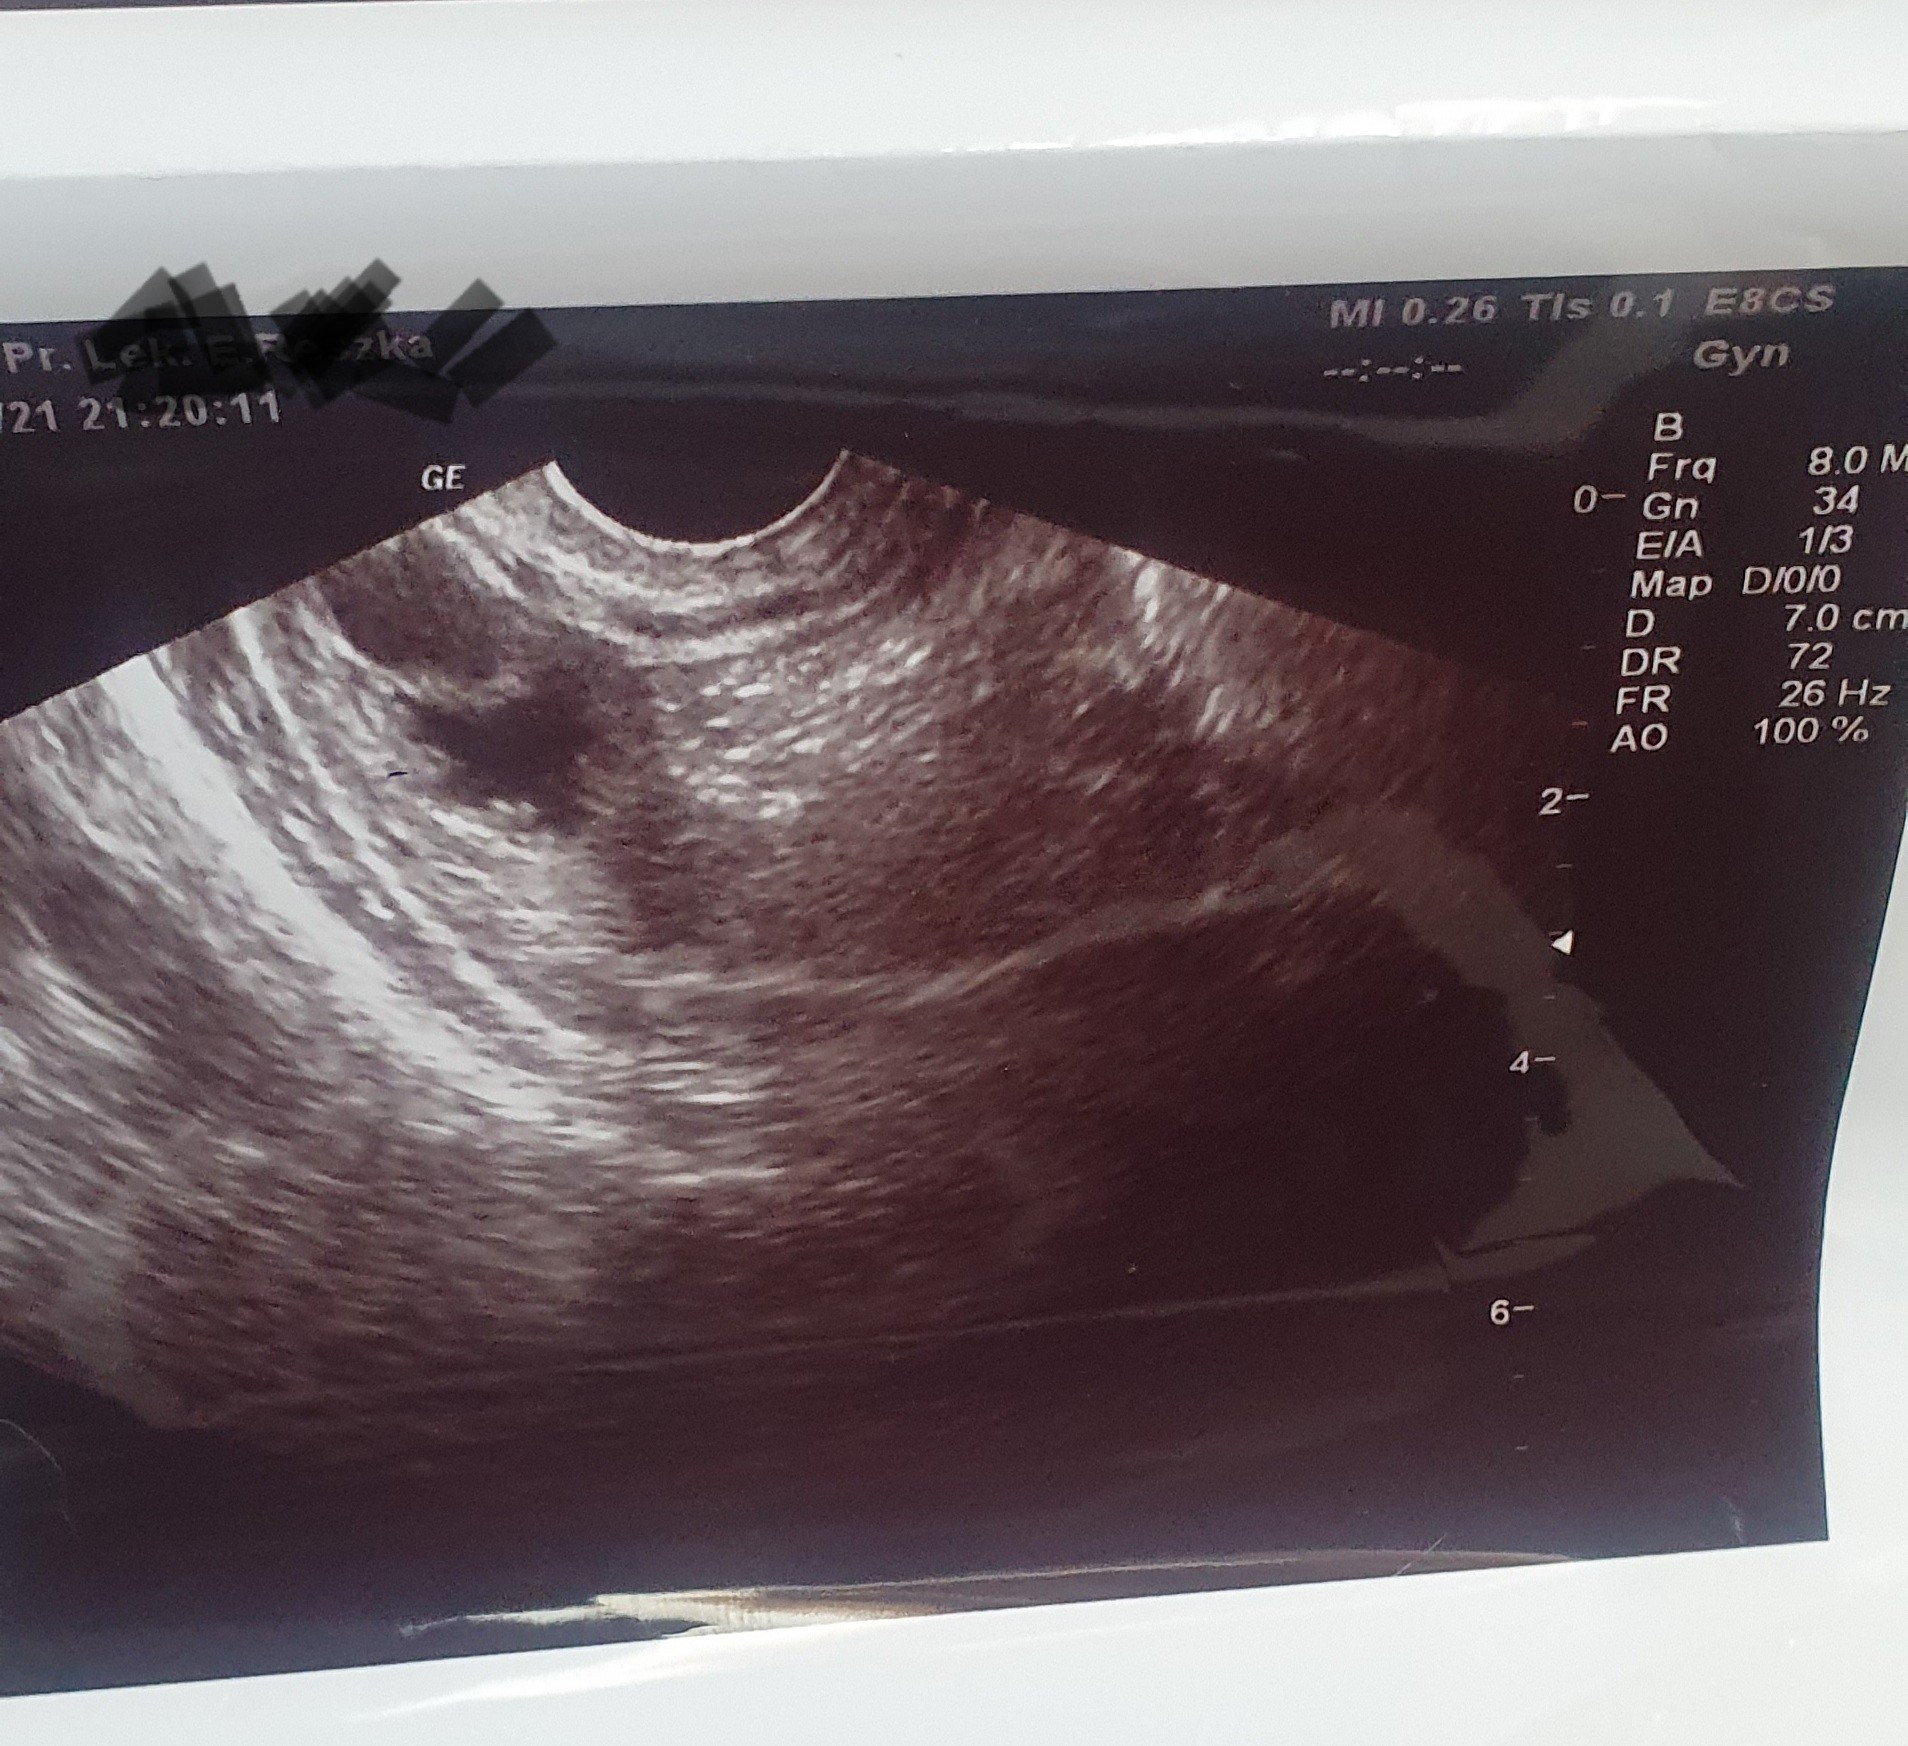

Zaczęłam się dziwnie czuć- Senna, przestało mi smakować mięso itp. Poszliśmy z narzeczonym do ginekologa prywatnie i powiedziała że ona ciazy nie widzi i czekać do następnej miesiączki i przyjść dwa tygodnie po jej terminie (nie dostałam żadnego opisu usg tylko standardowe 3 fotki). Akurat tak się trafiło że na NFZ 5.07.2021 miałam wizytę u tej samej doktor . Pomachała mi 3 razy w macicy , stwierdziła że endometrium powiększone jak na miesiączkę (na usg było widać jakbym miała jakblko w macicy), zleciła betę z krwi (na której wynik muszę czekać do wtorku a raczej środy bo wtedy mam wizytę). Przyznam wam się szczerze że nie raz robiono mi usg I nigdy nie widziałam takiego endometrium). Na tej wizycie nie dostałam żadnego opisu , zdjęcia a skierowanie lekarka dala położnej.

Ps . 10 .07 mam mieć niby miesiączkę ale nie czuję się na to . Przez ostatni tydzień przytyłam 3,300 - mam mddlosci , czasem zdarzy mi się zwymiotować (chociaż w zasadzie wygląda to na ulewanie niż wymiociny- małe ilości). Nie mogę patrzeć na mięso bo zaraz mnie mdli(a od zawsze byłam mięsożercą), często sikam. Wszystko się nasiliło od zeszłego tyg. Jedne testy wychodzą dodatnie , inne nie . Bardzo się boję, proszę o pomoc .